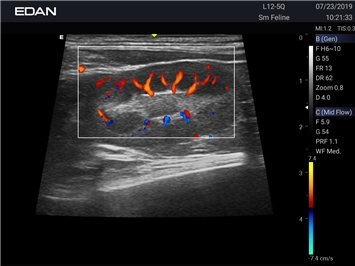

EDAN Acclarix AX2 VET

Ветеринарный ультразвук одним нажатием. Система Acclarix AX2 VET разработана с целью обеспечить бескомпромиссную производительность по доступной цене. Наличие уникальных двойных аккумуляторов в легком корпусе массой 4,5 кг из магниевого сплава позволяет системе Acclarix AX2 VET удовлетворять все потребности ветеринарных исследований, сохранив низкую стоимость.

EDAN Acclarix AX2 VET представляет собой специализированную ветеринарную ультразвуковую систему, сочетающую высокую производительность с доступной ценой. Благодаря продуманной конструкции и передовым технологиям, система обеспечивает качественную диагностику животных различных видов.

Цветовой допплер:

Да

Энергетический допплер: